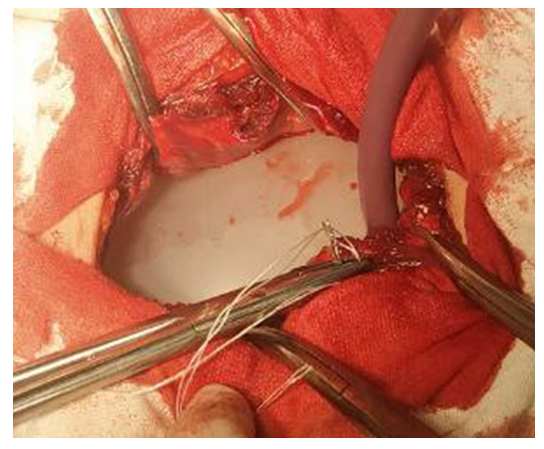

The study is based on the results of examination and treatment of 121 patients with ventral hernias and morbid obesity who underwent surgery in the surgical department of the 1st clinic of Samarkand State Medical University between 2015 and 2024. All patients underwent planned surgery, and depending on the chosen treatment approach, the patients were divided into two groups. The first group, the comparison group, consisted of 54 patients with ventral hernias and morbid obesity who underwent hernioplasty alone. The second, main group consisted of 67 patients who underwent hernioplasty combined with abdominoplasty.Of the 121 patients, 37 (30.6%) were men and 84 (69.4%) were women. Age distribution: up to 45 years - 22 (18.2%), 46-59 years - 67 (55.4%), 60-74 years - 29 (23.9%), 75-80 years - 3 (2.5%).All patients underwent anthropometry to determine their body weight. All patients had morbid obesity - alimentary in nature, due to dietary habits, combined with low physical activity. Excess body weight was assessed according to the WHO experts' classification. Patients were classified according to the A. Matarasso (1989) classification based on the degree of anterior abdominal wall ptosis. Minimal and moderate ptosis (I-II degree) was observed in 34 and 42 patients with obesity of the III-IV degree, respectively, in the studied groups. Moderate and severe ptosis (III-IV degree) was observed in 20 and 25 patients with III-IV degree obesity.Out of 121 patients with ventral hernias and morbid obesity, 90 (74.4%) had comorbid diseases. Among these, 49 patients had 1 additional pathology, 29 had 2, and 12 had 3 concomitant diseases of other organs and systems. Among comorbidities, cardiovascular diseases were the most common, occurring in 82.6% of cases, followed by respiratory system pathology in 9 (7.4%) patients, varicose veins of the lower extremities in 20 (16.5%) patients, and diabetes mellitus in 32 (26.4%) patients.According to the classification by Chervel J.P. and Rath A.M. (1999), the vast majority of patients (85 - 70.2%) had supraumbilical (M1) and periumbilical (M2) hernias. The lowest number of patients had lateral (L) 9 (7.4%) and combined (M+L) 3 (2.5%) ventral hernias. 46 (38.0%) patients had large (W3) and giant (W4) hernias. Out of 121 patients, 40 (33.0%) had primary ventral hernias, 50 (41.3%) had postoperative ventral hernias (R0), and 31 (25.6%) had recurrent ventral hernias (Rn).Among the instrumental research methods, computed tomography hernia abdominometry (CTHA) performed on 58 patients in the main group proved to be the most informative. CTHA made it possible to identify defects in the topography of the anterior abdominal wall, determine the relative volume of the hernia in relation to the abdominal cavity volume, plan adequate preoperative preparation, and choose the optimal method of repair. According to our studies, with a relative volume of the hernial protrusion up to 14.0% of the abdominal cavity volume, it is possible to use tension methods of hernioalloplasty - implantation of an "onlay" endoprosthesis with suturing of the defect.With a volume greater than 14.1%, preference was given to tension-free repair methods. In 46 (68.6%) patients of the main group with ventral hernias and morbid obesity at the preoperative stage, we conducted adaptive training to increase intra-abdominal pressure using the proposed improved pneumatic belt-bandage. The use of this technique in patients with ventral hernias W3-W4 and morbid obesity allowed for a reduction in the risk of developing compartment syndrome.In the comparison group (n=54), hernioalloplasty was performed using tension methods in 37 (68.5%) patients and tension-free methods in 17 (31.5%) patients.In the main group, the choice of hernia alloplasty was differentiated and supplemented with abdominoplasty according to our proposed program (certificate of state registration of the computer program No. DGU 10983, Intellectual Property Agency of the Republic of Uzbekistan - 2021). The patients in the main group were divided into 4 subgroups based on the program results.Patients in the 1st subgroup with a total score of up to 5, as well as with a hernia protrusion volume of up to 14% of the abdominal cavity volume according to CT hernia abdominometry data, underwent "onlay" mesh implantation with suturing of the hernia defect. This group consisted of 24 (35.8%) patients with morbid obesity and grade III-IV abdominoptosis, for whom hernia alloplasty was supplemented with abdominoplasty.In the 2nd subgroup, with a score of 6 to 10 and taking into account CT hernia abdominometry data showing a hernial protrusion volume greater than 14.1% of the abdominal cavity volume, we performed tension-free repair. To increase the volume of the abdominal cavity and prevent the development of abdominal compartment syndrome, after delimiting the abdominal cavity with a flap of the hernia sac, abdominal wall repair was performed by placing a mesh on the aponeurosis without suturing it. Mesh fixation was carried out using pre-placed U-shaped sutures encompassing all layers of the musculo-aponeurotic wall up to the peritoneum.In 12 (17.9%) patients of the 3rd subgroup of the main group with hernia defect sizes greater than 10 cm and hernia protrusion volumes exceeding 18% of the abdominal cavity volume, as determined by CT hernioabdominometry, a combined tension-free hernioplasty "onlay + sublay" was performed. This involved placing one implant behind the musculoaponeurotic layer after delimiting the abdominal cavity with a flap of the hernia sac, and positioning the second implant above the aponeurosis (Fig. 1). | Figure 1. Stages of endoprosthesis fixation"sublay" (1) and "onlay" (2) using pre-placed U-shaped sutures |